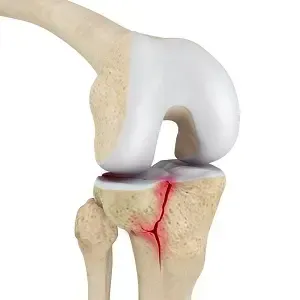

Een tibiaplateaufractuur is een breuk van het bovenste deel van het scheenbeen (tibia) waar het kniegewricht op rust. Dit bovenste gewichtsdragende deel van de tibia heet het tibiaplateau. Deze fractuur kan aan de buitenzijde (laterale tibiaplateau) voorkomen, aan de binnenzijde (mediale plateau) of aan beide zijden tegelijk (bicondylaire fractuur). Het plateau wordt als het ware ingedeukt door de femurcondyl (bovenzijde van de knie) die er bij de impact op drukt. Tibiaplateaufracturen ontstaan meestal door een forse kracht op het kniegewricht – bijvoorbeeld een val van hoogte op gestrekte benen, of een zijdelingse klap tegen de knie. Het zijn ernstige intra-articulaire fracturen, omdat het gewrichtsoppervlak aangedaan is en nauwkeurig herstel vereist om later goed te kunnen functioneren en slijtage te voorkomen.

Röntgenfoto’s: Hierop is de breuk van het tibiaplateau meestal zichtbaar: een verticale of schuine breuklijn door het laterale (buitenste) of mediale (binnenste) plateau, soms meerdere lijnen. Men kan vaak ook zien of er sprake is van indrukking: het gebroken plateau ligt dan lager dan normaal vergeleken met het andere plateau. Bij complexe fracturen ziet men losse fragmenten.